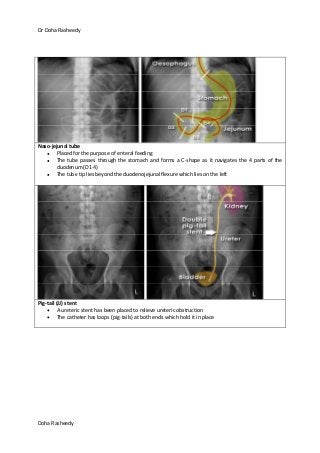

Naso-jejunal tube

Placed for the purpose of enteral feeding

The tube passes through the stomach and forms a C-shape as it navigates the 4 parts of the

duodenum (D1-4)

The tube tip lies beyond the duodenojejunal flexure which lies on the left

Pig-tail (JJ) stent

A ureteric stent has been placed to relieve ureteric obstruction

The catheter has loops (pig-tails) at both ends which hold it in place